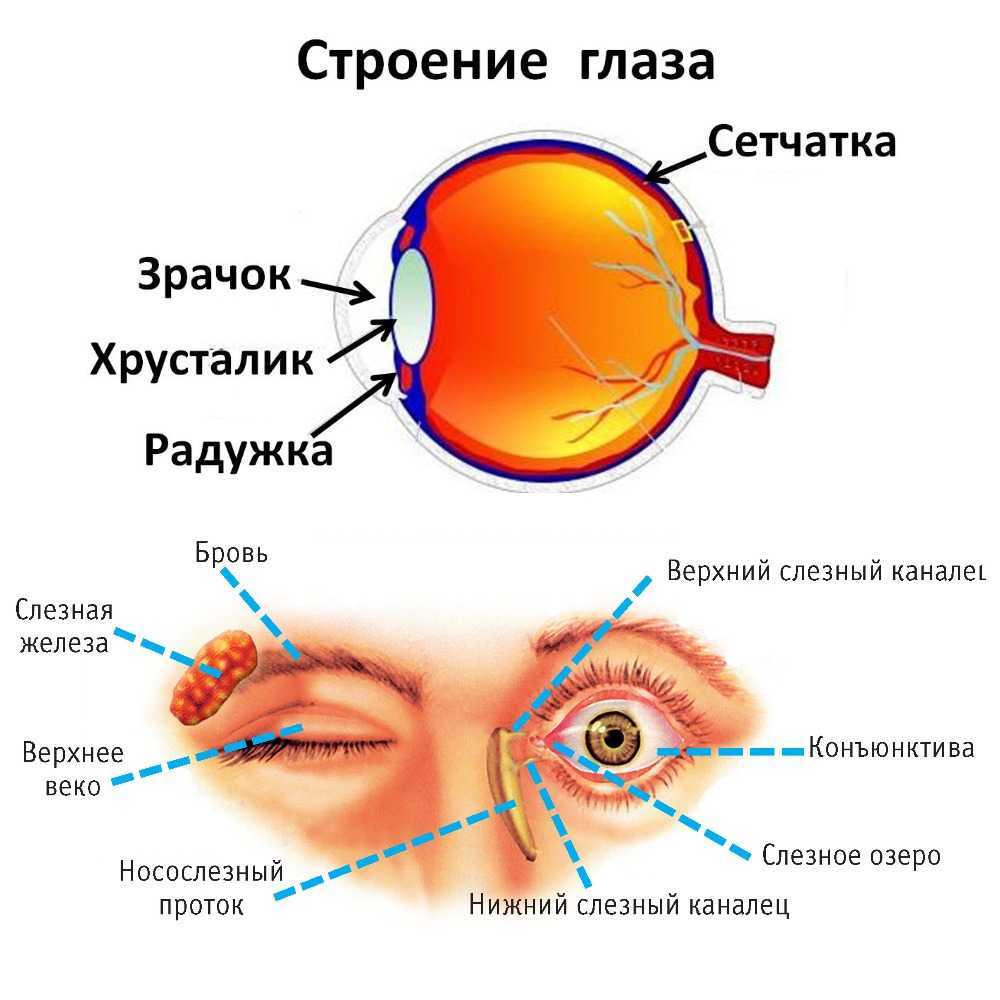

КТ-графики и изображение строения глаза